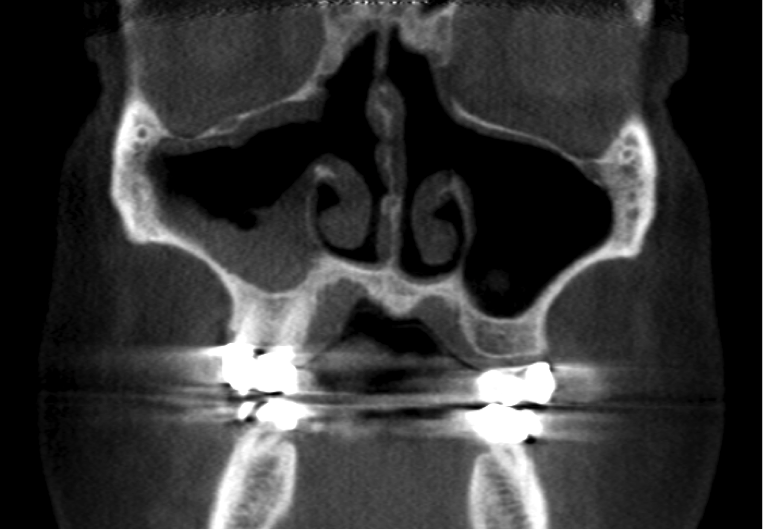

Other kinds of artifacts that are related to the CBCT technology itself may be present and compromise image quality, sometimes rather significantly.7 These artifacts are an inherent problem of CBCT and medical computed tomography because their appearance is a product of the reconstruction algorithms employed to compose the digital CBCT and CT images. In addition, the presence of any radiopaque materials is a frequent cause of artifacts. Metallic dental restorations, fixed prostheses, posts, and even gutta-percha may create artifacts that can obscure the visualization of the region of interest (Figure 3). As a result, fine diagnostic tasks may be impossible in proximity to restorations with high radiopacity. A number of CBCT manufacturers currently offer artifact reduction applications. These seem to have improved the resulting image quality; however, any possible gain in diagnostic efficiency has yet to be determined (Figure 4).

(3.) A CBCT coronal section of the maxillary sinuses showing severe metallic artifacts (horizon- tal, bright in appearance bands) originating from the crowns of the maxillary and mandibular teeth.

Figure 3